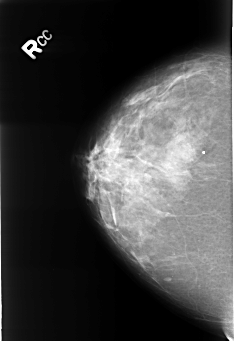

B_3247_1.RIGHT_MLO

RIGHT_MLO LINES 4488 PIXELS_PER_LINE 3032 BITS_PER_PIXEL 12 RESOLUTION 50 NON_OVERLAY